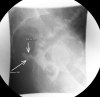

Management of the acute anastomotic leak is complex and patient-specific. Clinically stable patients often benefit from a nonoperative approach utilizing antibiotics with or without percutaneous drainage. Clinically unstable patients or nonresponders to conservative management require operative intervention. Surgical management is dictated by the degree of contamination and inflammation but includes drainage with proximal diversion, anastomotic resection with end-stoma creation, or reanastomosis with proximal diversion. Newer therapies, including colorectal stenting, vacuum-assisted rectal drainage, and endoscopic clipping, have also been described.